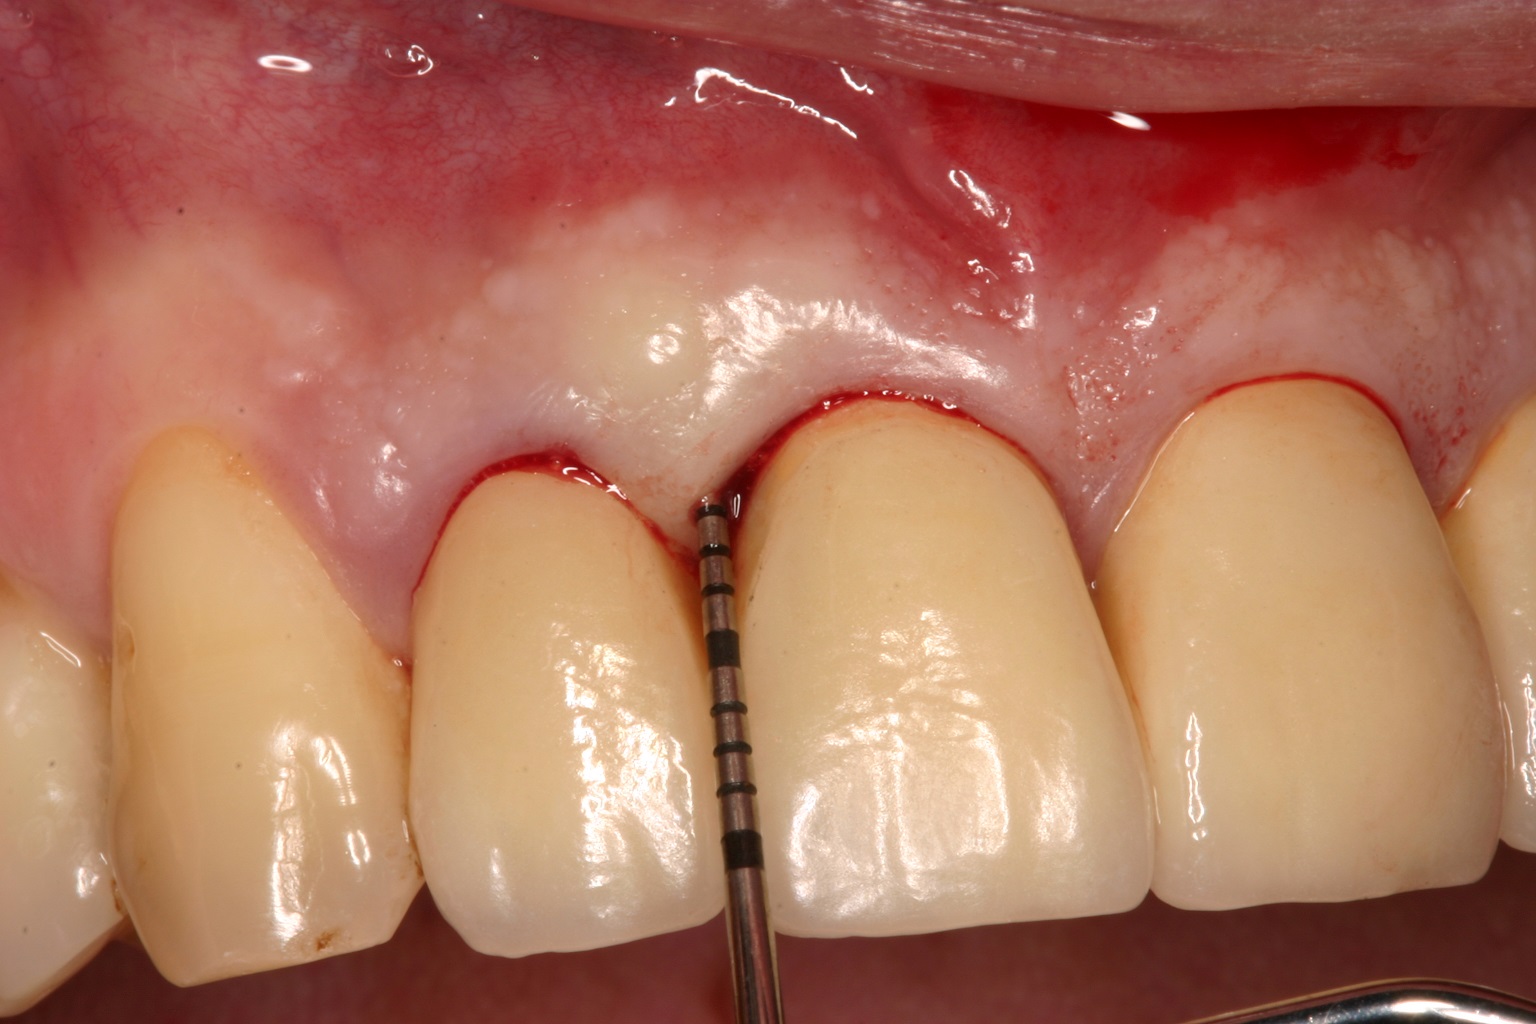

03/08 - Minimal buccal flap reflection according to simplified papilla preservation flap technique (Cortellini et al. Int J Periodontics Restorative Dent. 1999). The intra-operative view shows a deep intrabony defect distal on tooth 11.Non-contained intrabony defect treated with the simplified papilla preservation flap in conjunction with Straumann® Emdogain® and a particulate bone grafting material - Prof. Dr. Dr. A. Kasaj